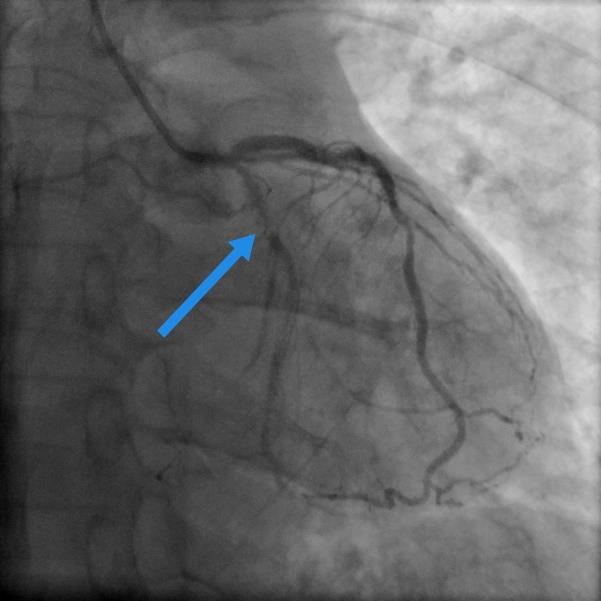

左图术前旋支狭窄95%(箭头处),右图术后狭窄完全消失。